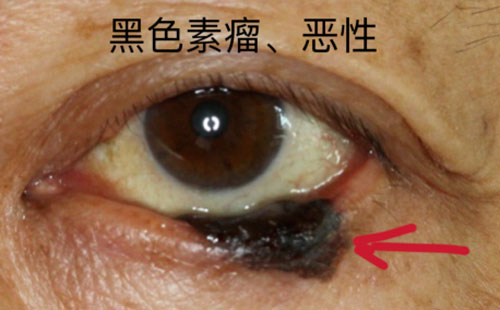

眼肿瘤包括眼睑、结膜、眼内、泪器、眼眶肿瘤。眼睑恶性肿瘤常见基底细胞癌,睑板腺癌、鳞状细胞癌和黑色素瘤,良性肿瘤常见于色素痣和血管瘤;眼眶肿瘤包括淋巴瘤、腺样囊性癌、海绵状血管瘤、神经鞘瘤、神经纤维瘤等;眼内肿瘤以恶性多见,主要见于视网膜母细胞瘤、脉络膜黑色素瘤、脉络膜转移癌等。

对于眼睑的肿瘤,会充分考虑到颜面部的美容需要,在确保清除病变的同时,完成整形修复。眼睑肿瘤表现多种多样,良性病变多生长缓慢,边界清楚。但是如肿块突然增长加速,有破溃、出血,疼痛,色素性肿块有色素播散现象时,您必须引起高度重视。绝大部分恶性肿瘤都发生在中老年人,而年轻人的眼睑肿块多是炎症变化。

如果您到医院就诊,医生借助放大仪器可以更清楚地观察病变。部分恶性病变的早期难以完全凭临床经验确诊,医生会建议您手术活检,通过病理来确诊。若是恶性,手术切除治疗是首选疗法,切除的范围取决于肿块的大小、位置、深度。皮片移植或皮瓣转移、游离带结膜脸板移植、口唇或聘粘膜移植等方法可以修复肿瘤切除后遗留的巨大缺损。眼睑“寸土寸金”,即使肿块只相差1毫米,手术也会由简变繁,所以早治疗是重中之重。